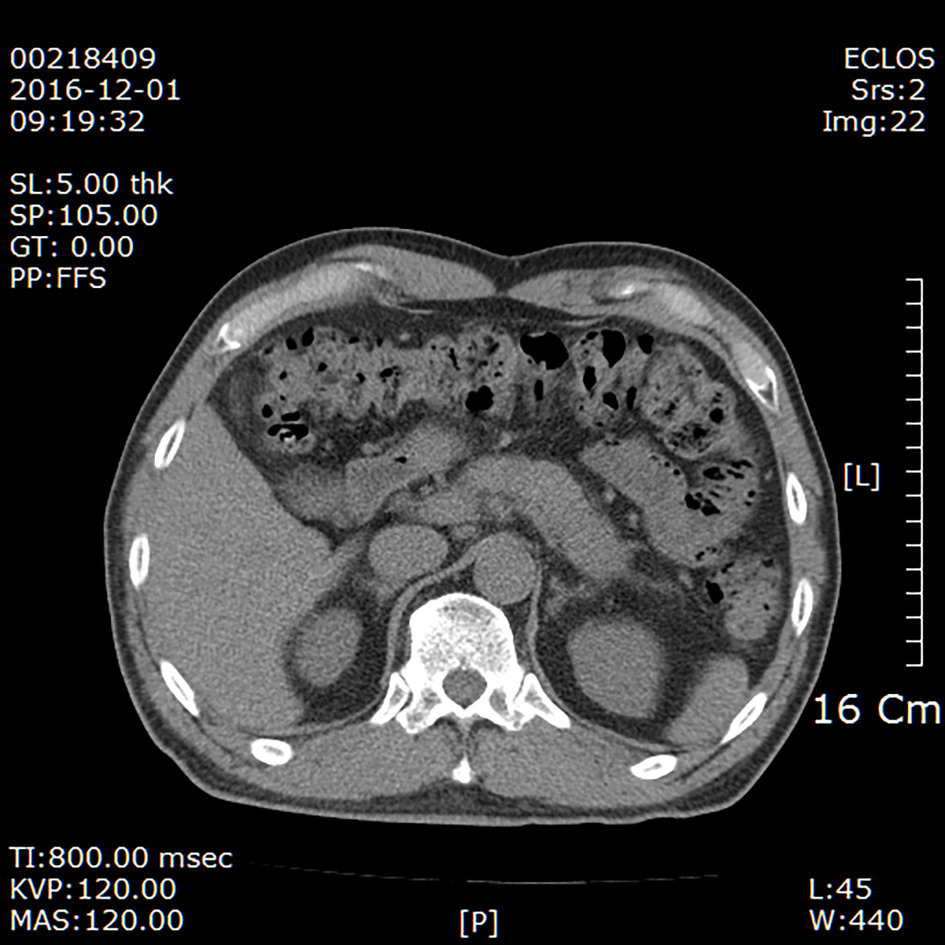

췌장암 진단법은 크게 복부초음파와 ct, mri (자기공명영상)가 있다. 소화불량 복통 있으면 ct 검사로 체크. 국립암센터에 따르면 췌장암 진단 후 5년 이상 생존자는 2017년 1월 기준으로 1913명이다. 이 중 654명은 10년 넘게 살고 있다. 췌장암은 근치적 수술이 매우 어려운데다 발견 시기도 늦어 5년 생존률이 낮고, 기존 약물의 효과가 크지 않은 대표적인 난치성 암이다. 실제 미국 뉴욕의대 종양내과 전후근 교수팀이 발표한 '암 환자의 식욕부진과 영양상태' (2006년)라는 논문을 보면, 췌장암 환자의 영양실조. 그래서 암종 중 상대생존율이 가장 낮은 암이기도 하다. 2002 한·일 월드컵 4강 신화의 주역 유상철 전 인천 유나이티드 감독이 췌장암으로 세상을 떠났다.

소화불량 복통 있으면 ct 검사로 체크. 유상철 인천 유나이티드 감독이 췌장암 4기인 것으로 알려져 많은 이들의 안타까움을 사고 있다. 유상철 감독님은 황달기가 심상치 않아서 김영선 원장 (사진=민트병원 제공) 민트병원 이미징센터 김영선 원장 (영상의학과 전문의/복부 세부전공)은 복부 초음파검사는 몸의 깊숙한 곳에 위치한 데다 위, 소장, 대장으로 가려진 췌장의 특성상 전체를 제대로 확인하기 어려울 수 있다며 ct와 mri는 고해상도 촬영이 가능해 췌장 전체를 확인할. 소화 불량에 체중까지 준다면…췌장암 가능성 체크해야.